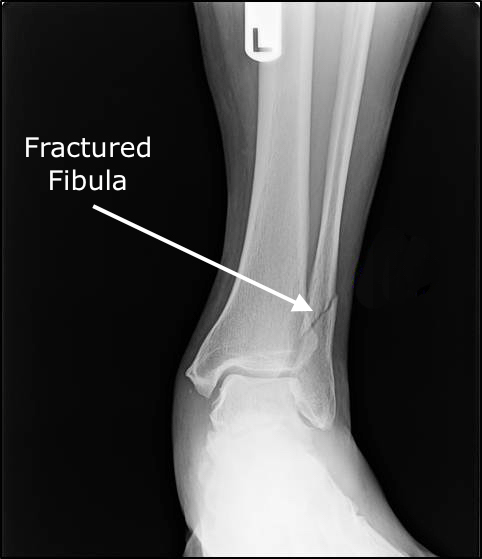

Bone Fractures

Bone fractures, colloquially referred to as broken ankle, are common injuries in or around the ankle joint and in the foot, being a common cause of ankle pain. Bone fractures can happen as a consequence of an impact or another traumatic injury. The severity of bone fractures is variable and will determine the type of treatment needed. Immobilization with cast is generally required, but fracture stabilization with orthopedic pinning or open joint surgery may be necessary.